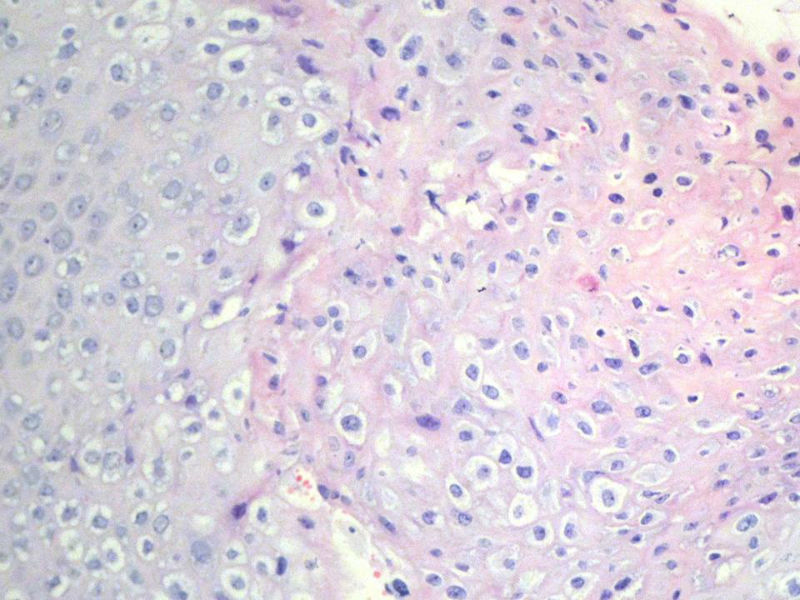

男,72岁,右耳听力下降两个月,检查右外耳道有黄豆大肿物,表面乳头状,手术切除。

乳头状瘤,有轻度异形,有恶变倾向

乳头状瘤,轻度异形,有恶变倾向

乳头状瘤,上皮内可见挖空样细胞,建议HPV检测

鳞状上皮乳头状瘤,未发现恶性变。